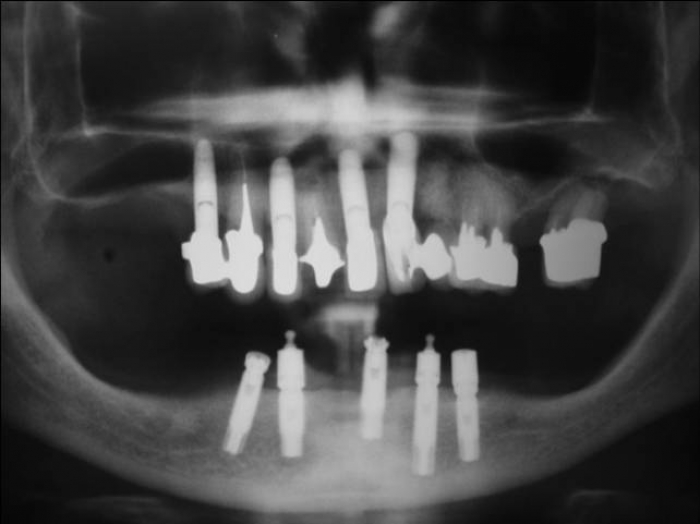

Raio X com implantes Cone Morse e próteses fixas em porcelana